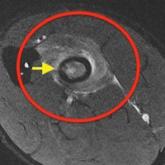

Radial Shaft Stress Fracture in a Major League Pitcher

In athletes, the incidence of stress fractures has been reported to be 1.4% to 4.4%.1 Stress fractures of the upper extremity are less...